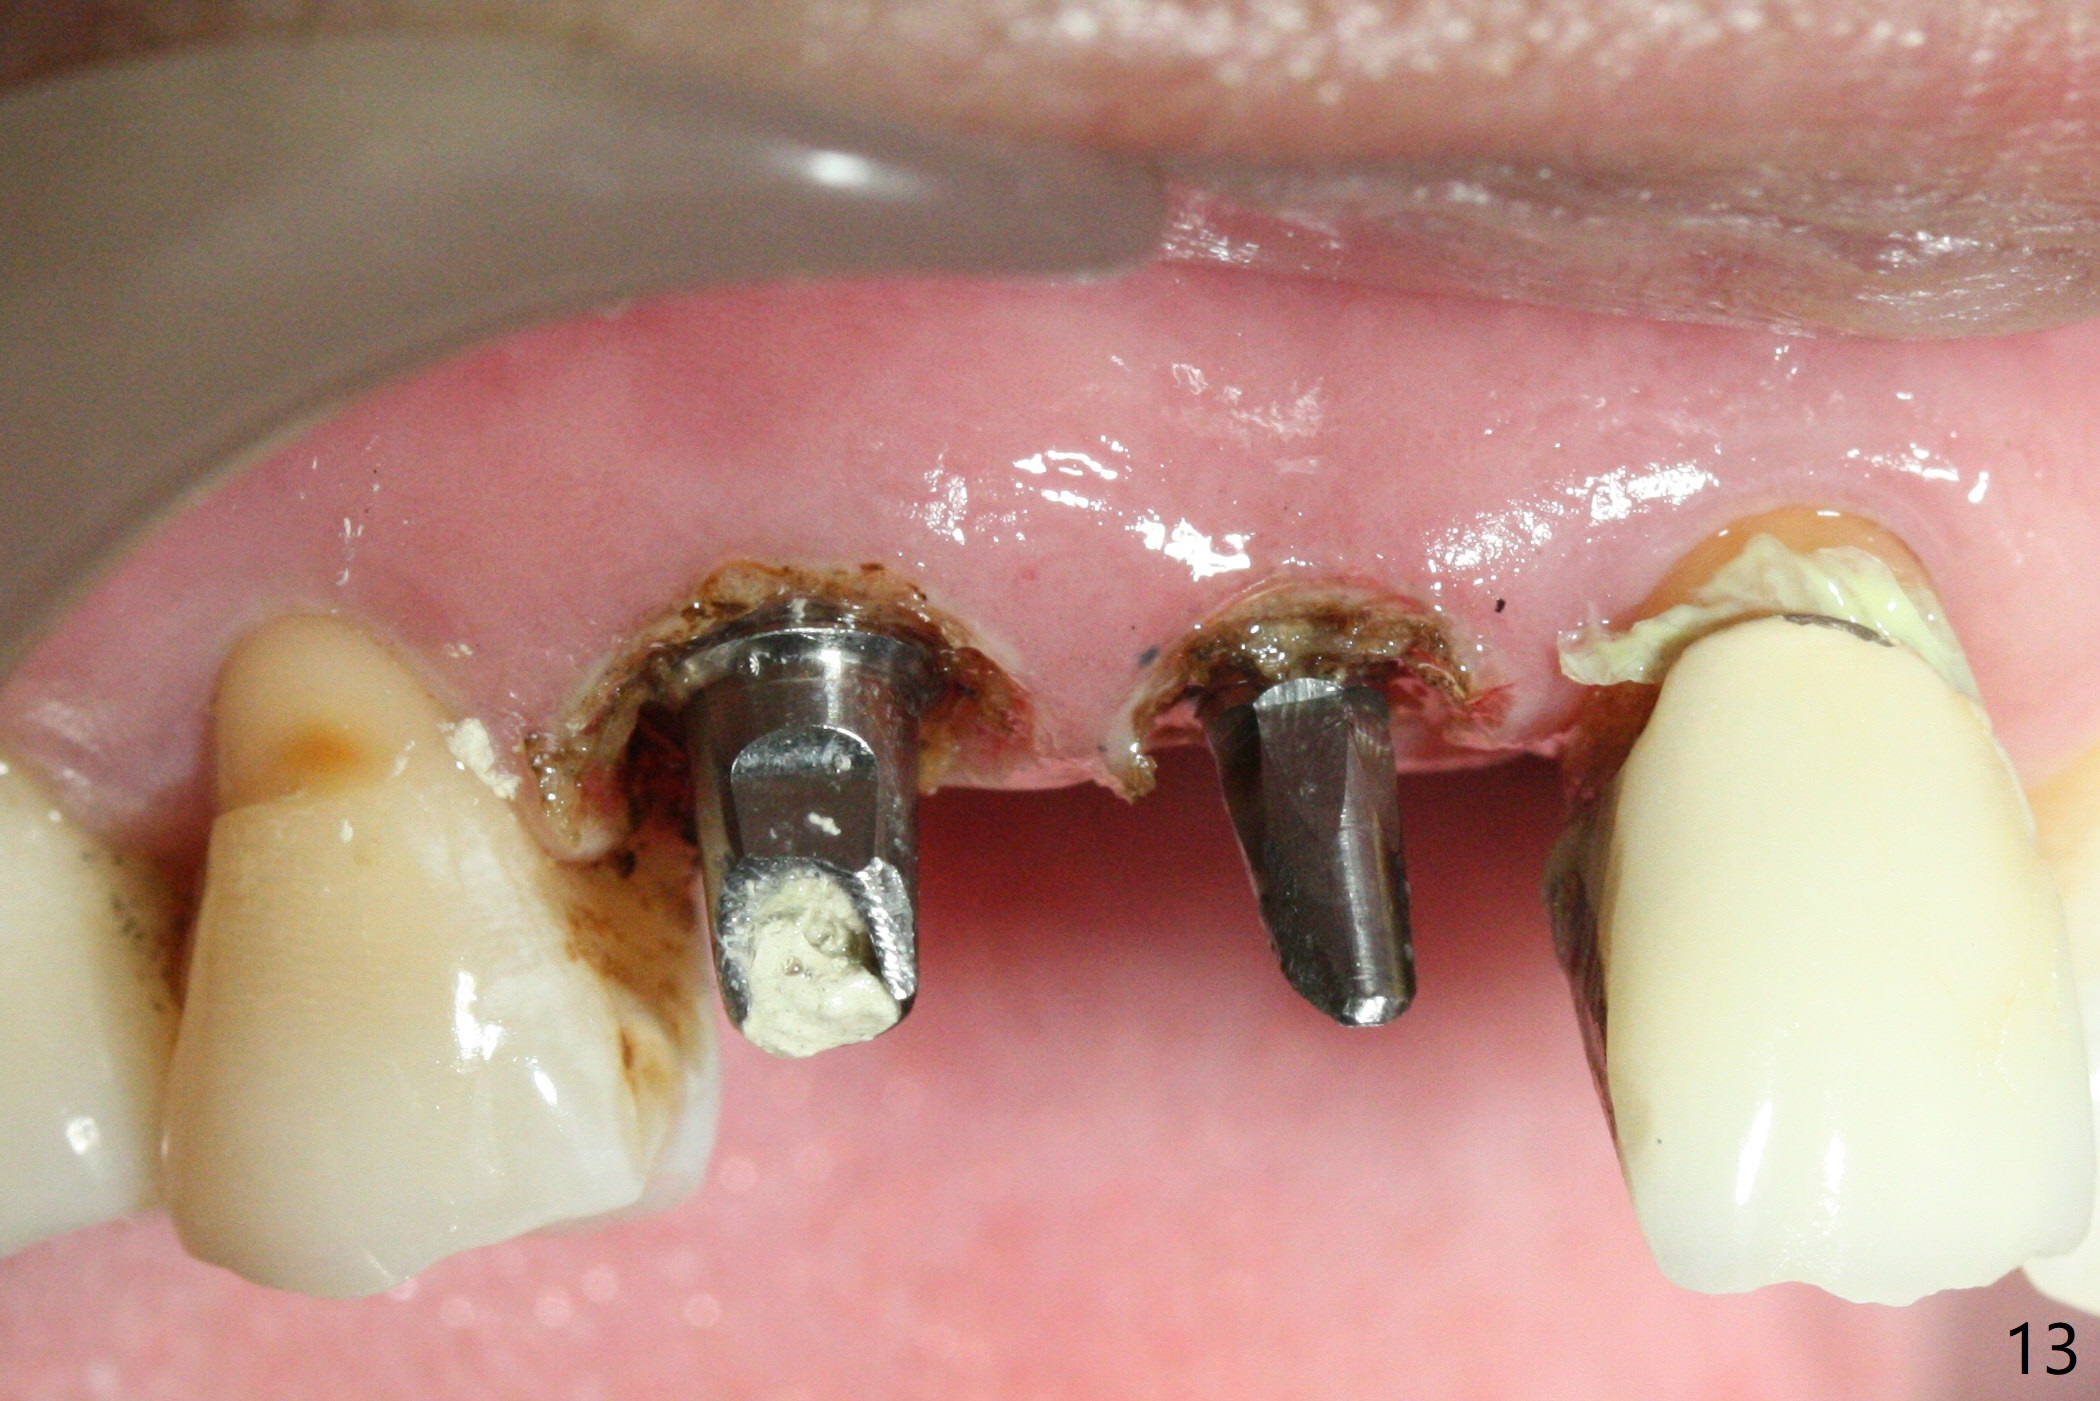

When the bridge is sectioned between #7 and 8, the tooth #6 is found non-salvageable (Fig.1). Incision shows the atrophic buccal plate at #7 (Fig.2 arrowheads); to prevent the same feature from happening at #6 with thin buccal plate, the most buccal portion of the root is preserved (socket shield (Fig.2-4: *)). The initial osteotomy is established in the palatal slope at #6 (Fig.5 circle) with 1.5 mm drill (Fig.6,7). A portion of the root is visible in Fig.6 (arrowheads). After sequential osteotomy with 2 mm, 3 mm (Fig.8) and 3.2 mm drills, a 4x15 mm implant is placed (Fig.10). To accommodate the cross bite, the coronal portion of the implant (Fig.9 white circle) is positioned close to the socket shield. It appears that the shield prevents the implant from encroaching the buccal plate.

Since the ridge at #7 is ~ 4 mm, a 2.5x14 mm 1-piece implant is placed (Fig.8) after 1.2 mm (Fig.7), and 1.5 mm drills at 12 mm and 2 mm drill at 8 mm. Later the implant is placed deeper (Fig.10). There is no bone loss 7 or 12 months postop, respectively (Fig.11,12). After Diode gingivectomy, there is papillary formation (Fig.13). No provisional is provided after impression (with the abutment torqued at #6) for oral hygiene. With access holes at #6 and 7, crowns are bonded with minimal residual cement (Fig.14 <, which is removed later). There is no hard (Fig.15,16) or soft (Fig.17 *) atrophy 26 months postop, i.e., 13 months post cementation, due to the presence of socket shield (Fig.15 <, as compared to Fig.1). In fact the tooth #8 has mobility and fremitus (short root/poor crown/root ratio, Fig.16); occlusal adjustment is done 13 months post cementation. The crown is dislodged 2 years 1 month post cementation; a prefabricated post is being tried in (Fig.18). There is no atrophy, bone loss or infection at #6 (with socket sheath (*)) or 7 two years 5 months post cementation (Fig.20-27).